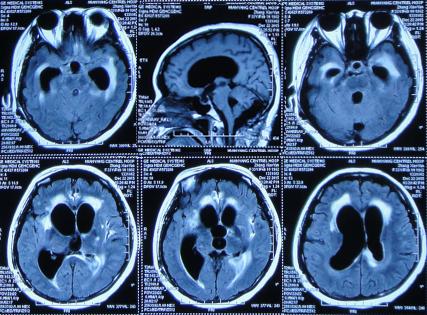

患者于2015年7月31日,无明显诱因突发头痛发热症状,体温升高至38.6℃,因自行服药3天后无改善即2015年8月3日,就诊并住入第1家的位于四川省成都市某军医院的神经内科,查头MRI示“右侧小脑半球结节影,环性强化”(图-1)。

图-1:2015年8月3日头部MRI